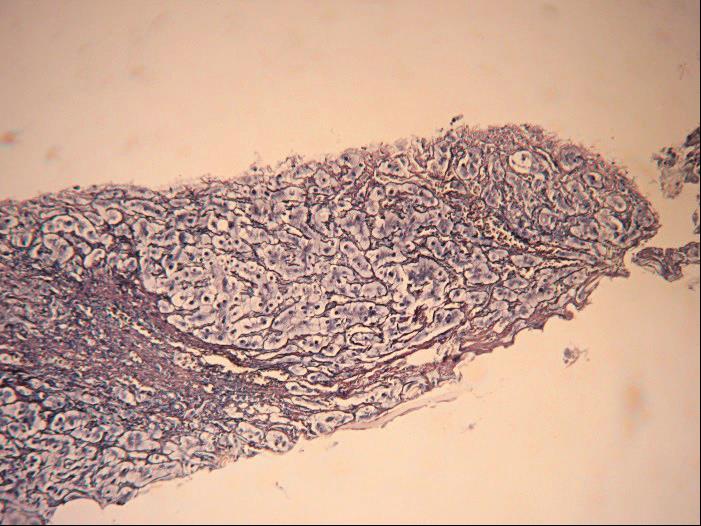

(1)窦周纤维化:

窦周纤维化(PSF)或称细胞周围纤维化(PCF),在酒精性肝病较为弥漫。正常窦周主要为纤细网状纤维(C-Ⅲ),仅在肝窦分叉处有少量C-Ⅰ,均不插入肝细胞间。酒精性肝病时,由于HSC活化增生广泛,引起窦周纤维化(PSF)亦较广泛(图4-3-3)。窦周纤维化按程度分为轻、中、重三度。

图4-3-3 酒精性肝病

酒精性肝纤维化,广泛窦周纤维化伴纤维间隔形成,部分小叶结构紊乱(网状纤维染色)